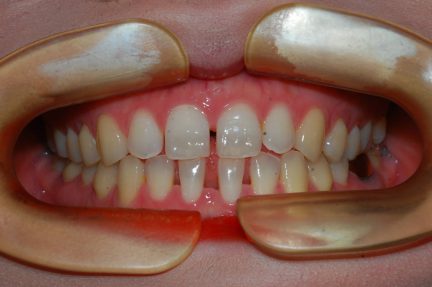

État final

- Relation de Classe I obtenue

- Surplomb et recouvrement normaux obtenus

- Arcades alignées et coordonnées

- Ligne esthétique du sourire obtenue

- Cas où tous les objectifs de traitement ont été atteints

- Arcades harmonieuses obtenues